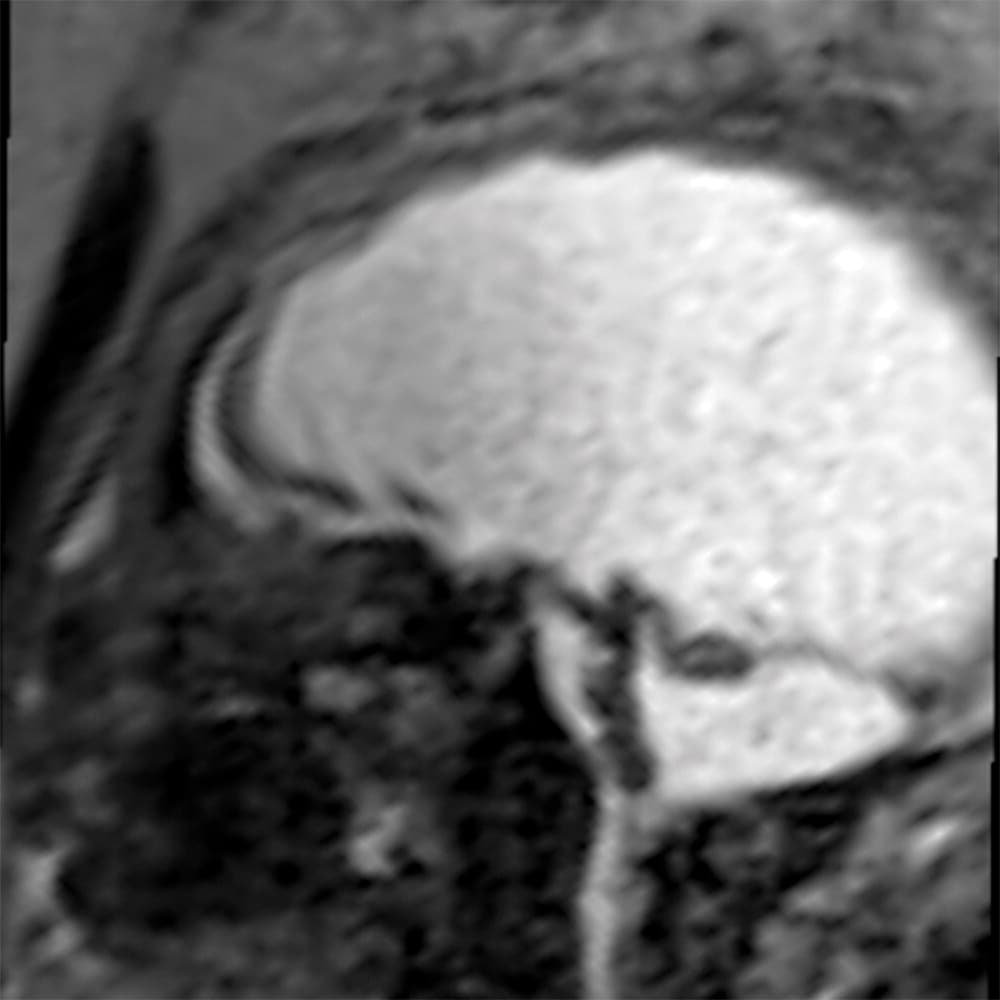

Investigadores brasileños difundieron este martes el mayor número hasta ahora disponible de imágenes computarizadas, resonancias magnéticas y ultrasonidos, de bebés y fetos infectados con el virus del Zika. El daño es mucho mayor del que anticipaban.

Así describe la radióloga brasileña Fernanda Tovar-Moll lo que vio al analizar centenares de imágenes computarizadas, resonancias magnéticas y ultrasonidos de 45 bebés que se contagiaron de zika en el vientre materno en el estado de Paraíba, en el noreste del país, donde el brote ha sido severo.

La mayoría nació con microcefalia, cuya característica más llamativa es que tienen el cerebro y la cabeza más pequeña. Pero muchos sufren una escala y severidad de daño mucho peor en partes importantes del cerebro como el cuerpo calloso, que conecta los dos hemisferios; el cerebelo, que juega un papel significativo en el movimiento, equilibrio y habla; y los ganglios basales, que controlan el pensamiento y la emoción.

Tovar-Moll es coautora de un estudio publicado el martes en la revista Radiology y fue liderado por la doctora Patricia Soares de Oliveira-Szejnfeld, a quien se le da crédito por establecer el vínculo entre el zika y la microcefalia en Brasil.